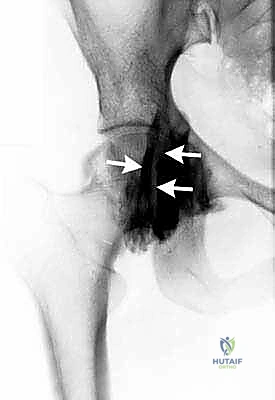

- الأشعة السينية (X-rays): لاستبعاد وجود كسور، التهاب مفاصل (خشونة)، أو تشوهات عظمية (مثل الاصطدام الفخذي الحُقي).

- الموجات فوق الصوتية الديناميكية (Dynamic Ultrasound): أداة ممتازة لأنها تسمح للطبيب برؤية حركة الأوتار مباشرة أثناء قيام المريض بالحركة التي تسبب الطقطقة، مما يؤكد التشخيص الفوري لالتهاب الأوتار أو الجراب.

- التصوير بالرنين المغناطيسي (MRI) أو (MR Arthrogram): هو المعيار الذهبي لتشخيص النوع داخل المفصلي. يوفر صورًا عالية الدقة للغضاريف، الشفة الحرقفية، والأنسجة الرخوة. يتم حقن صبغة داخل المفصل أحيانًا لإبراز التمزقات الدقيقة.